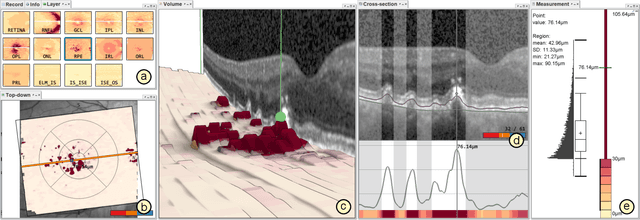

Advances in optical coherence tomography (OCT) have enabled noninvasive imaging of substructures of the human retina with high spatial resolution. OCT examinations are now a standard procedure in clinics and an integral part of ophthalmic research. The interpretation of the OCT helps ophthalmologists understand the impact of various retinal and systemic diseases on the structure of the retina in a way not previously possible. In the early stages of retinal diseases, however, the identification and analysis of small and localized substructural changes in the retina remains a challenge. We present an overview of novel visual analytics approaches for the interactive exploration of early retinal changes in single and multiple patients, the comparison of the changes with normative data, and automated quantification and measurement of diagnosis-relevant information. We developed these approaches in close collaboration with ophthalmology researchers and industry experts from a leading OCT device manufacturer. As a result, they not only significantly reduced the time and effort required for OCT data analysis, especially in the context of cross-sectional studies, but have also led to several new discoveries published in biomedical journals.